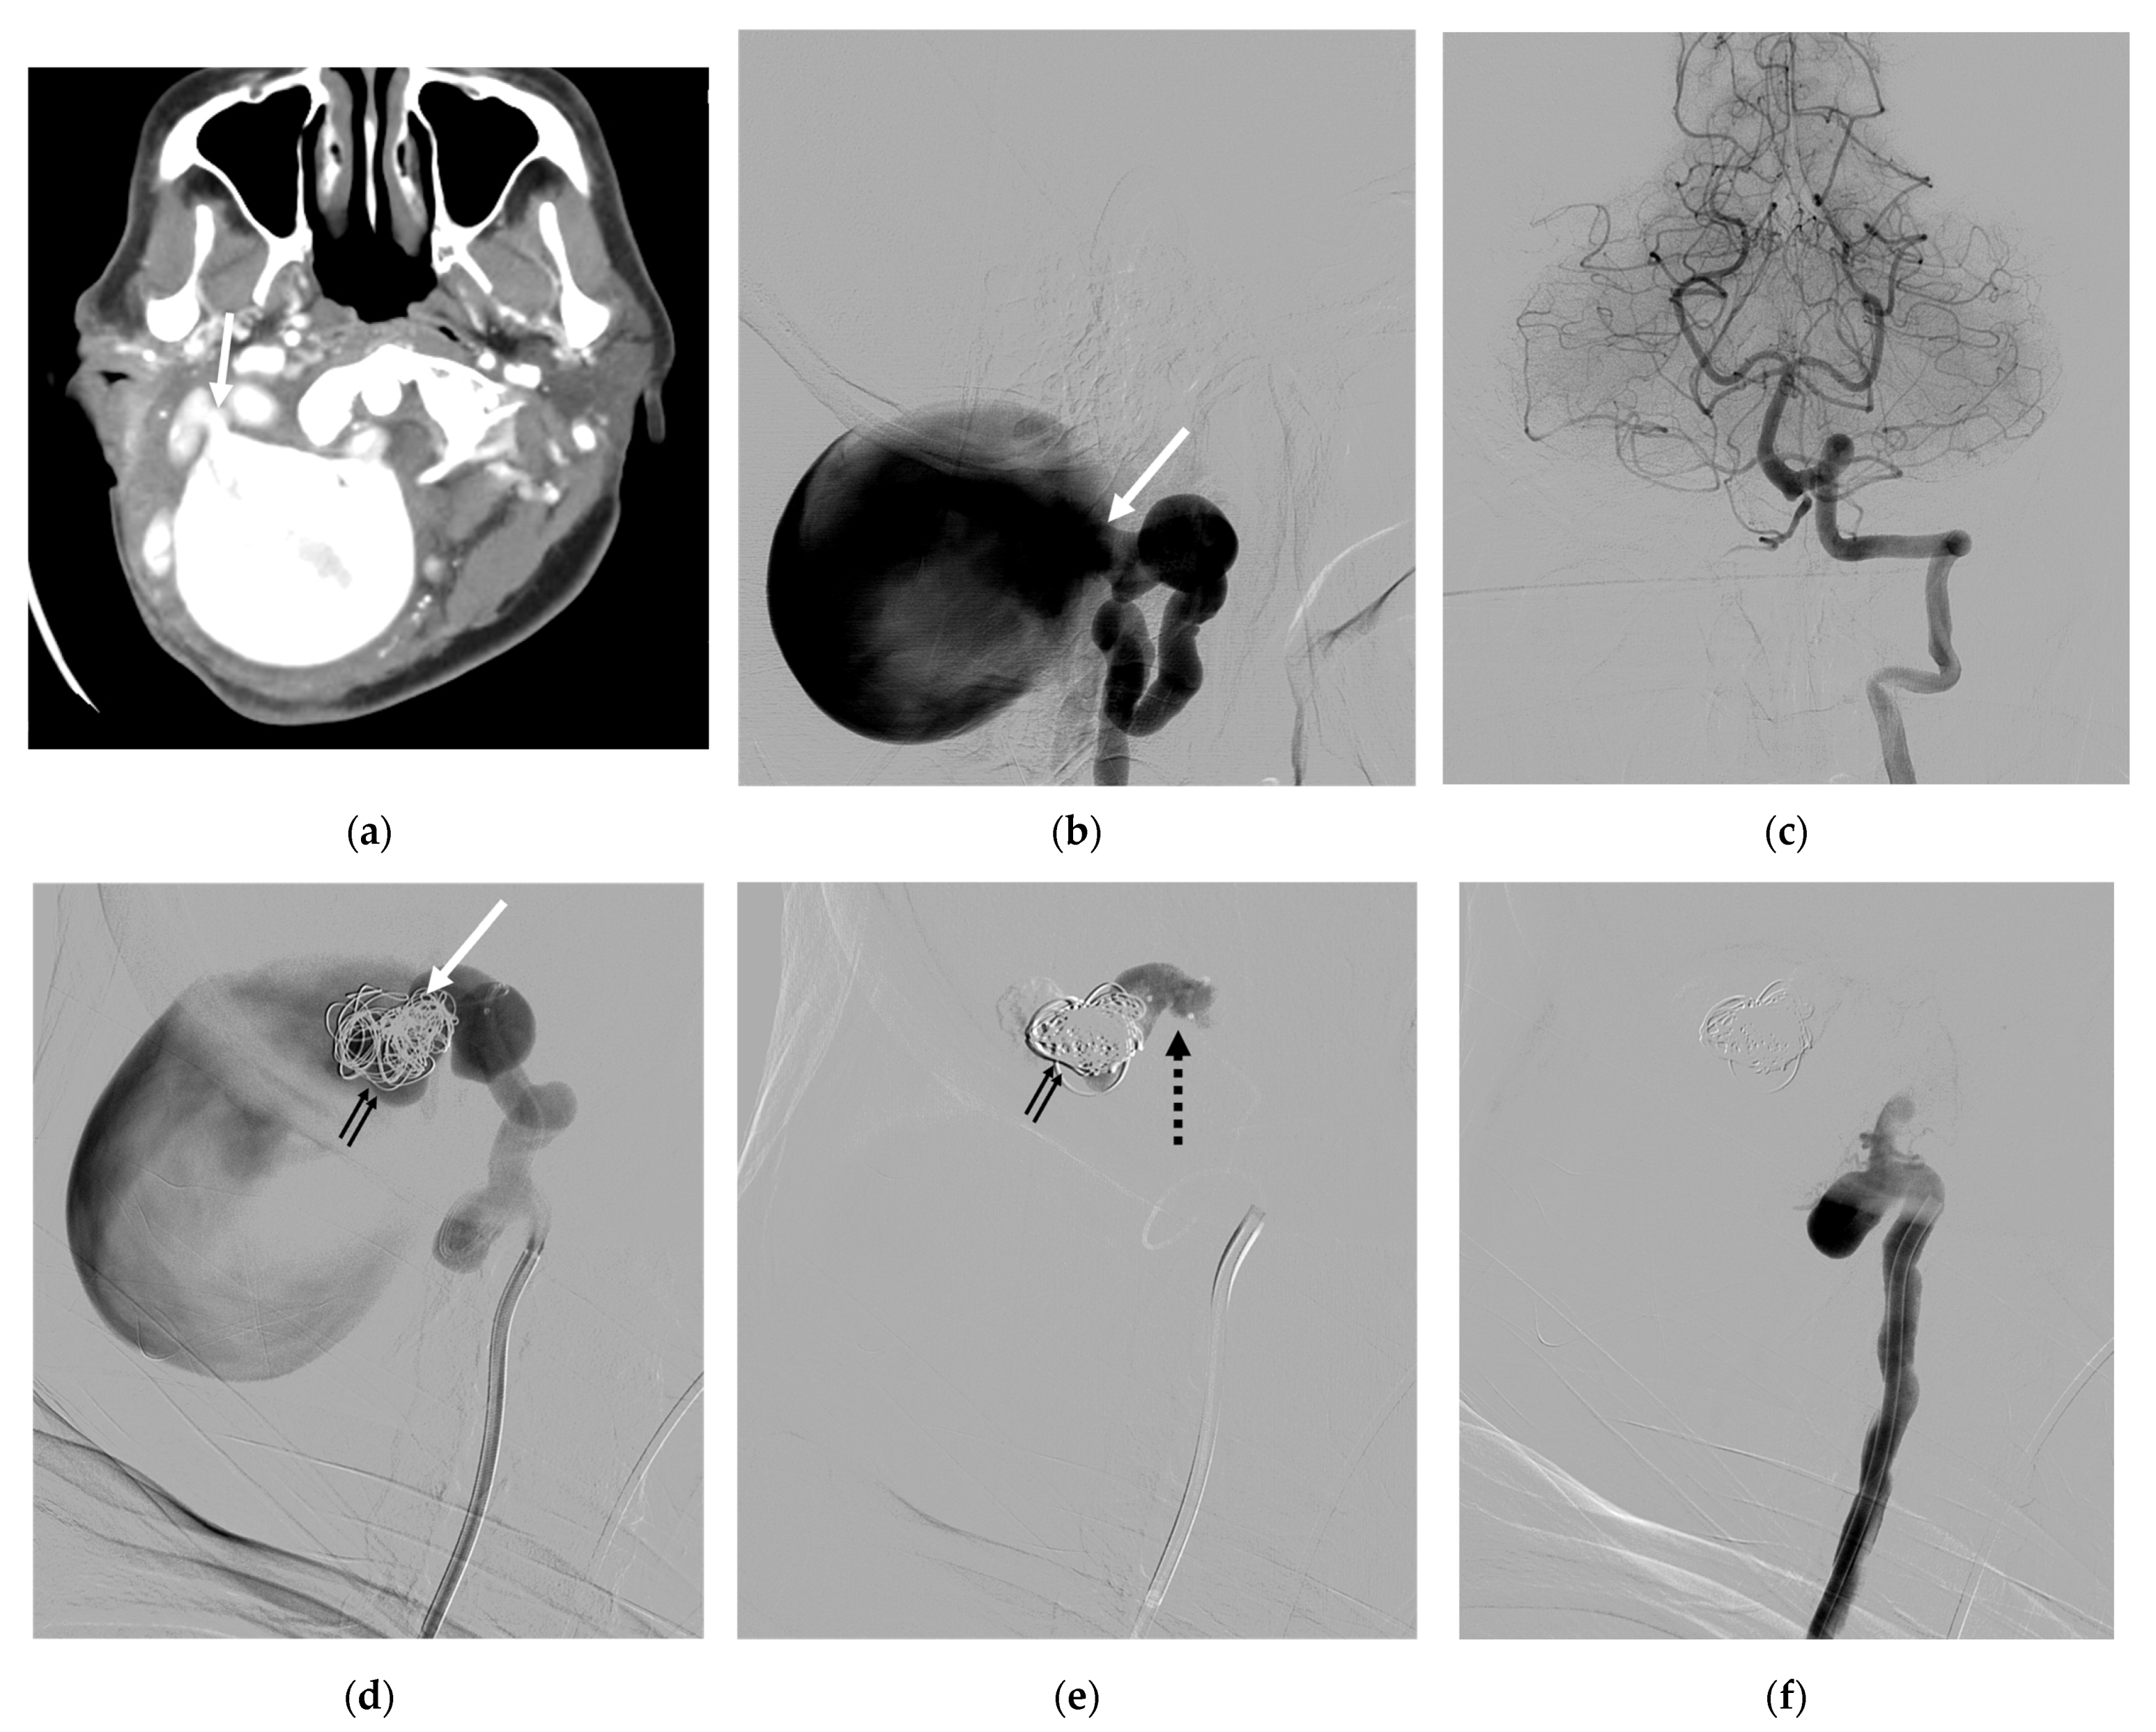

| 8 | F | 33 | Neck mass; tinnitus; paresthesia of left arm; ataxia | NF-1 | S | IJV; VVP with venous pouch | Y | B, C, and NBCA | O | Improved | Vertigo |

| 9 | F | 25 | Neck mass | NF-1 | S | VVP with venous pouch | Y | C and NBCA | O | Improved | None |